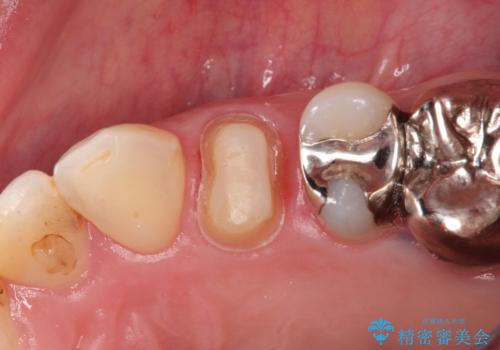

大きい虫歯 根管治療〜オールセラミッククラウン

- 大きな虫歯を認めた患者様です。

自発痛を認めたことから、不可逆性歯髄炎の診断を行い治療を介入しております。

根管治療した場合は速やかに被せ物による修復が必要です。